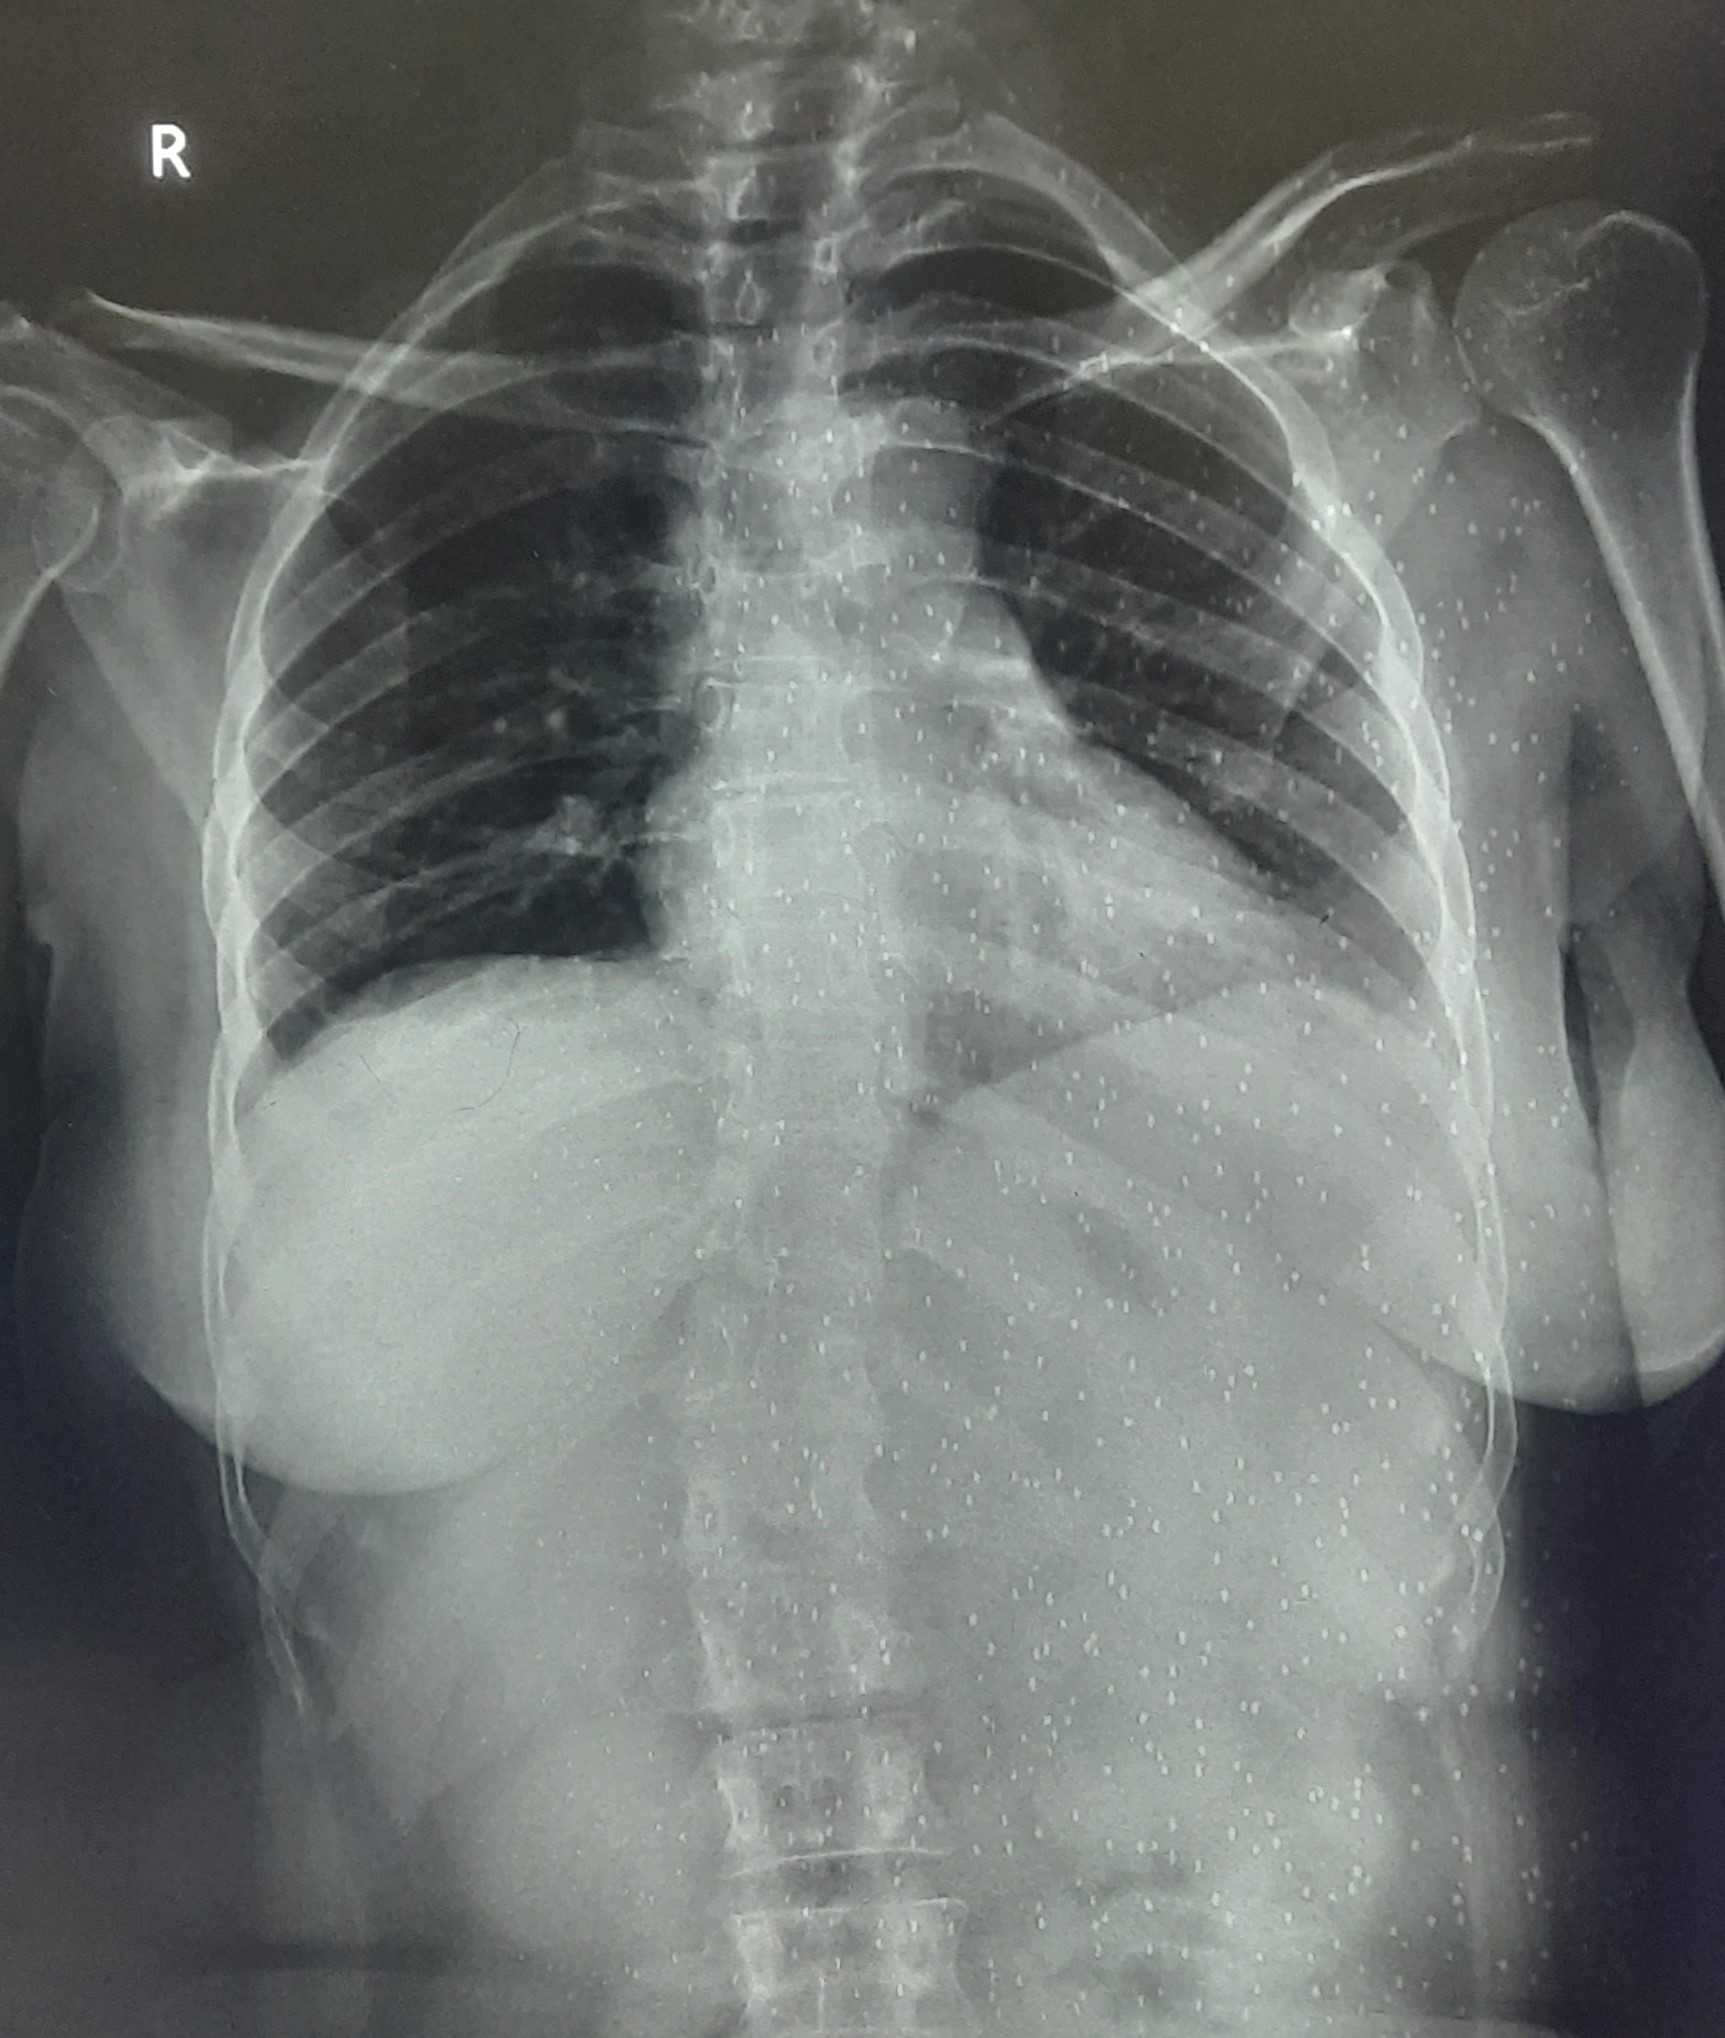

| 219 | IGGMC, Nagpur, Nagpur | P2 | 29-4253 | BACCHO CHAUDHARI | Consent taken on Paper | 47 Yrs. |

Provisional Diag : MILLIARY TB

Final Diag : BILATERAL INFILTRATION WITH MILLIARY SHADOWS |

TB Case (Confirmed) | BILATERAL INFILTRATION WITH MILLIARY SHADOWS | Abnormality visible on x-ray |